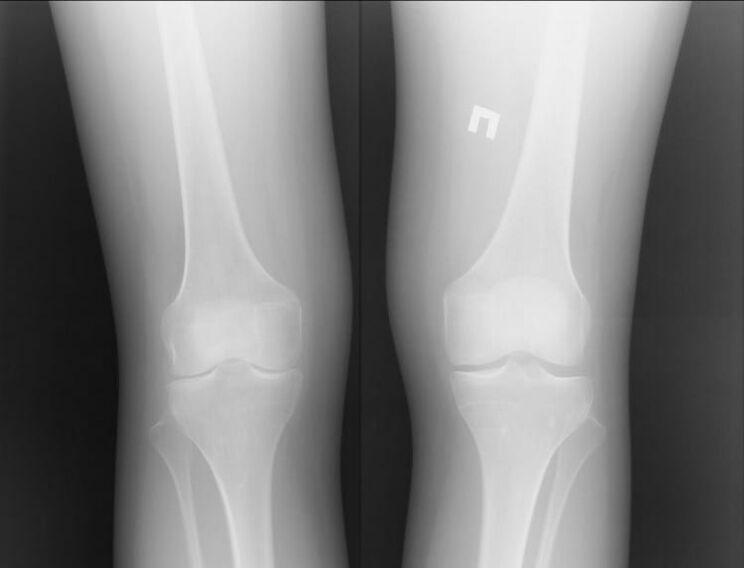

Rendgen koljena pogođena artrozom

Artroza je bolest zgloba uzrokovana problemima u hrskavici. Počinju se postupno raspadati i razbiti, što dovodi do nepodnošljive boli. Javlja se i u akutnim i u dugoročnim oblicima. Često se pojavljuje ujutro ili nakon teške tjelesne aktivnosti.

Simptomi artroze

Artroza je većim dijelom kronična bolest. Dugo vremena možda ne razumijete da imate ovu bolest, jer se ona očituje u obliku privremene boli. Međutim, može nastaviti ili brzo ili polako. Ako artroza nije otkrivena u vremenu u ranim fazama, ova će bolest dovesti do invaliditeta. Simptomi artroze:

1. Oteklina u periartularnom području. S artrozom dolazi do drugačije situacije: zglob nabubri samo tijekom akutne bolesti. Bolest se javlja u pratnji jake boli.

2. Drobljenje i osjećaj krhkosti u zglobu. Od prvih minuta, drobljenje ne smeta posebno vlasniku, ali ako se ne poduzmu tretman, drugi će ga čuti. Osjećaj krhkosti često se javlja nakon tuširanja ili plivanja u hladnoj vodi.

3. Crtanje boli. To je posebno istinito kada postoji stres na pogođenom zglobu. Na primjer, prilikom penjanja stepenicama.

Uglavnom, artroza se pojavljuje iz teških opterećenja ili ozljeda. Bolna bol može se pojačati noću i nastaviti do jutra.